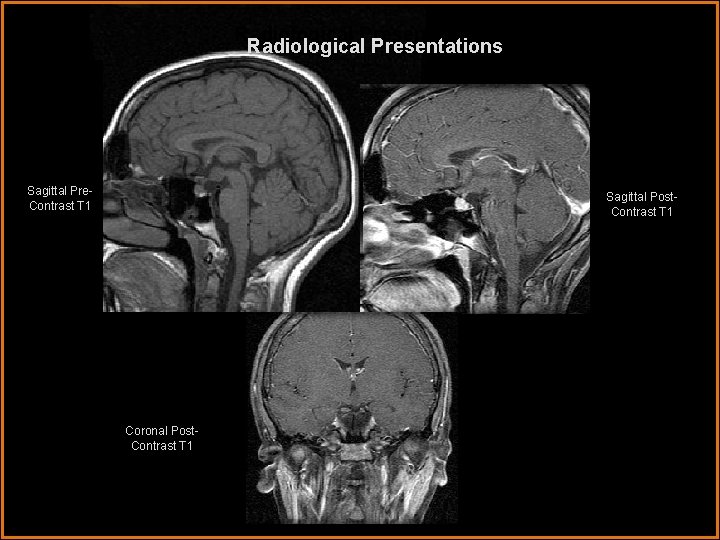

Radiological Presentations Sagittal Pre. Contrast T 1 Sagittal Post. Contrast T 1 Coronal Post. Contrast T 1

Findings and Differentials Findings: MRI reveals a well-circumscribed mass eccentrically located in the region of the hypothalamus. The mass is iso-intense to gray matter on T 1 weighted images and hyperintense to gray matter on T 2 weighted images. Post-contrast images demonstrate no significant enhancement. Differentials: • Craniopharyngioma • Optic glioma • Hypothalamic hamartoma

Discussion Patients typically present with precocious puberty. Other symptoms include visual disturbances and the characteristic “gelastic seizure”, or laughing seizure. These masses are homogeneous and iso-intense to gray matter on T 1, and hyperintense to gray matter on T 2 imaging. They do not enhance. The anatomic location together with the signal characteristics is strongly suggestive of the diagnosis. The optic nerves and chiasm are separate from the mass, excluding an optic nerve glioma. Craniopharyngiomas often have calcifications, cystic components and hemorrhage, a feature lacking in these hamartomas. Hyypothalamic gliomas typically enhance after contrast. The long term stability with failure to grow and continued lack of enhancement would support the diagnosis of hypothalamic hamartoma. Shah P, Patkar D, Patankar T, Shah J, Srinivasa P, Krishnan A. MR imaging features in hypothalamic hamartoma: a report of three cases and review of literature. J Postgrad Med 1999; 45: 84 -6